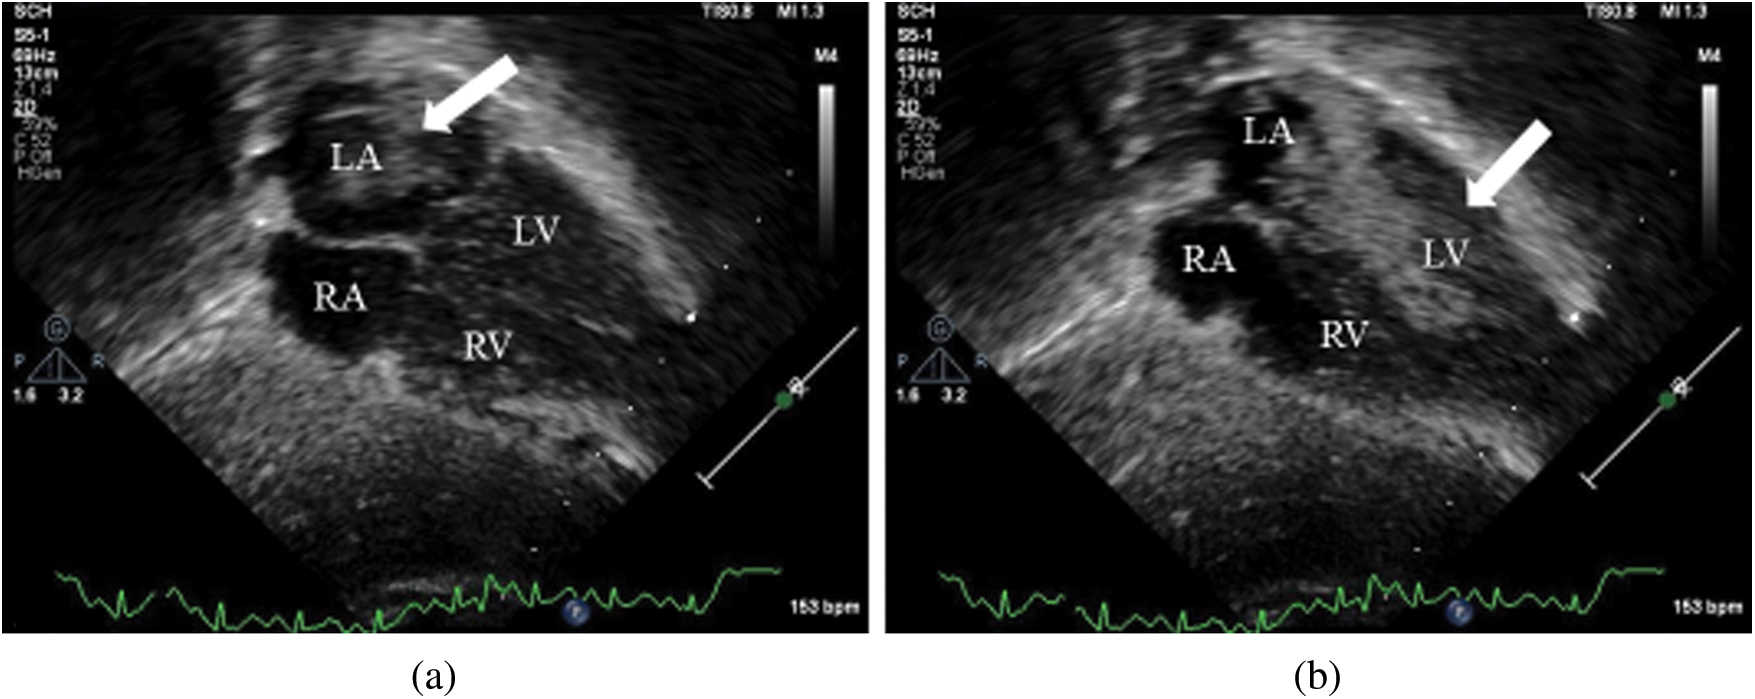

After discharge, further progression in ventilator weans was limited by persistent episodic hypoxemia at home. Over time, the patient’s parents noted a pattern of reproducible cyanosis with head turn to the right, which they demonstrated for providers at a follow up appointment in pulmonary clinic when the patient was 24 months old. The positional hypoxemia was not associated with hypoventilation (no changes in end-tidal CO2 or exhaled tidal volumes) and was not responsive to supplemental oxygen, but improved with return of head to neutral position, raising concern for a position-dependent shunt. Review of past echocardiograms suggested a possible PLSVC in the absence of a dilated coronary sinus. Saline contrast echocardiography with injection in the left arm showed vigorous contrast return to the left atrium, suggestive of a PLSVC to left atrial connection (Fig. 1). This was further confirmed on cardiac MRI for surgical planning, demonstrating a PLSVC draining into the left atrium with a small bridging vein between the right and left superior vena cavae. With the patient’s head turned to the right, there was a 50% decrease in flow in the right SVC and a compensatory increase in flow in the left SVC (Fig. 2).

Figure 1: Subxiphoid views from contrast echocardiography with left arm injection site showing (a) contrast in the left atrium (arrow) and (b) contrast subsequently flowing between the left atrium and the left ventricle during diastole (arrow)